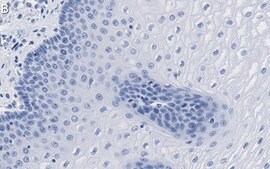

Immunohistochemistry (Paraffin) Analysis: A 1:1,000 dilution from a representative lot detected Involucrin in human esophagus tissue sections.